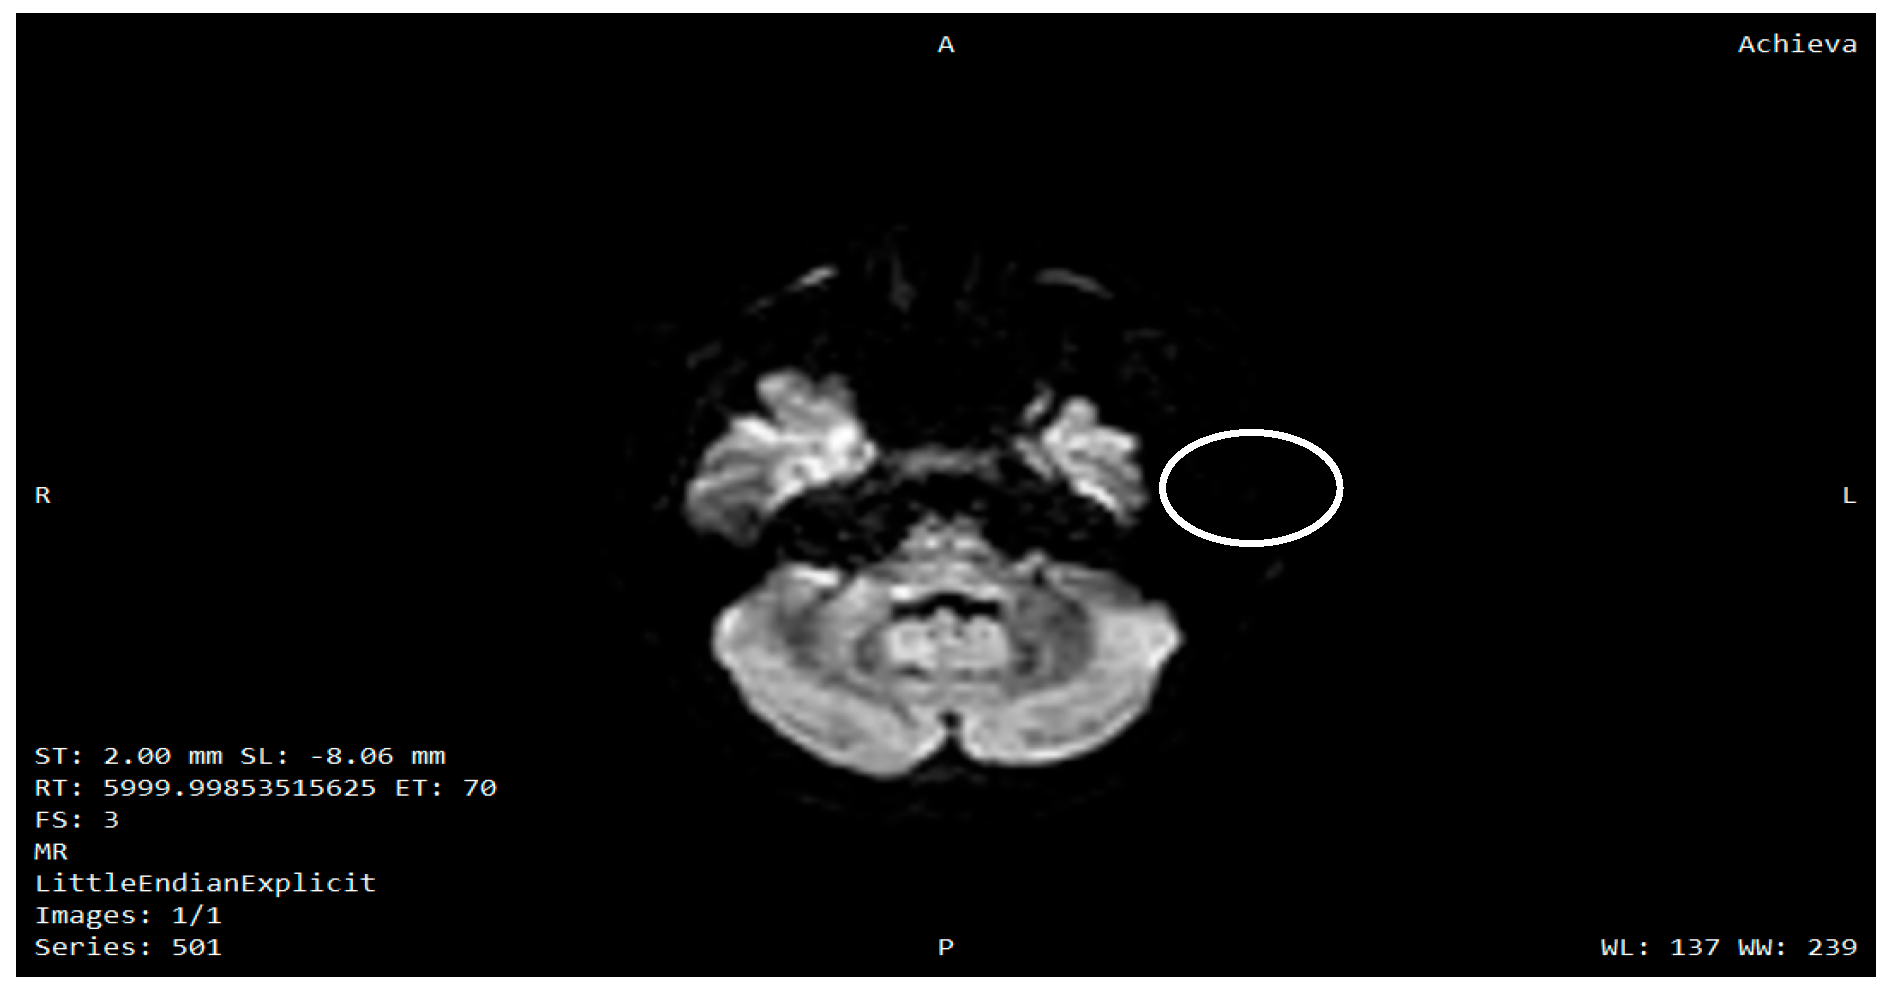

- Samara, A.; Lugar, H.M.; Hershey, T.; Shimony, J.S. Longitudinal assessment of neuroradiologic features in Wolfram syndrome. AJNR Am. J. Neuroradiol. 2020, 41, 2364–2369. [Google Scholar] [CrossRef]

- Lugar, H.M.; Koller, J.M.; Rutlin, J.; Eisenstein, S.A.; Neyman, O.; Narayanan, A.; Chen, L.; Shimony, J.S.; Hershey, T. Evidence for altered neurodevelopment and neurodegeneration in Wolfram syndrome using longitudinal morphometry. Sci. Rep. 2019, 9, 6010. [Google Scholar] [CrossRef] [PubMed]

- Hershey, T.; Lugar, H.M.; Shimony, J.S.; Rutlin, J.; Koller, J.M.; Perantie, D.C.; Paciorkowski, A.R.; Eisenstein, S.A.; Permutt, M.A. Early brain vulnerability in Wolfram syndrome. PLoS ONE 2012, 7, e40604. [Google Scholar] [CrossRef] [PubMed]